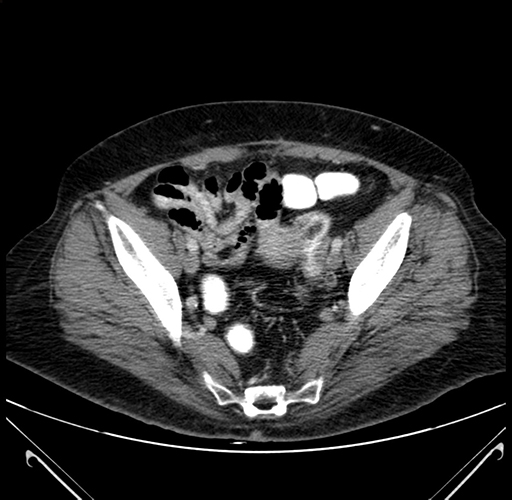

Pre-Chemo: Axial Venous

Axial Venous